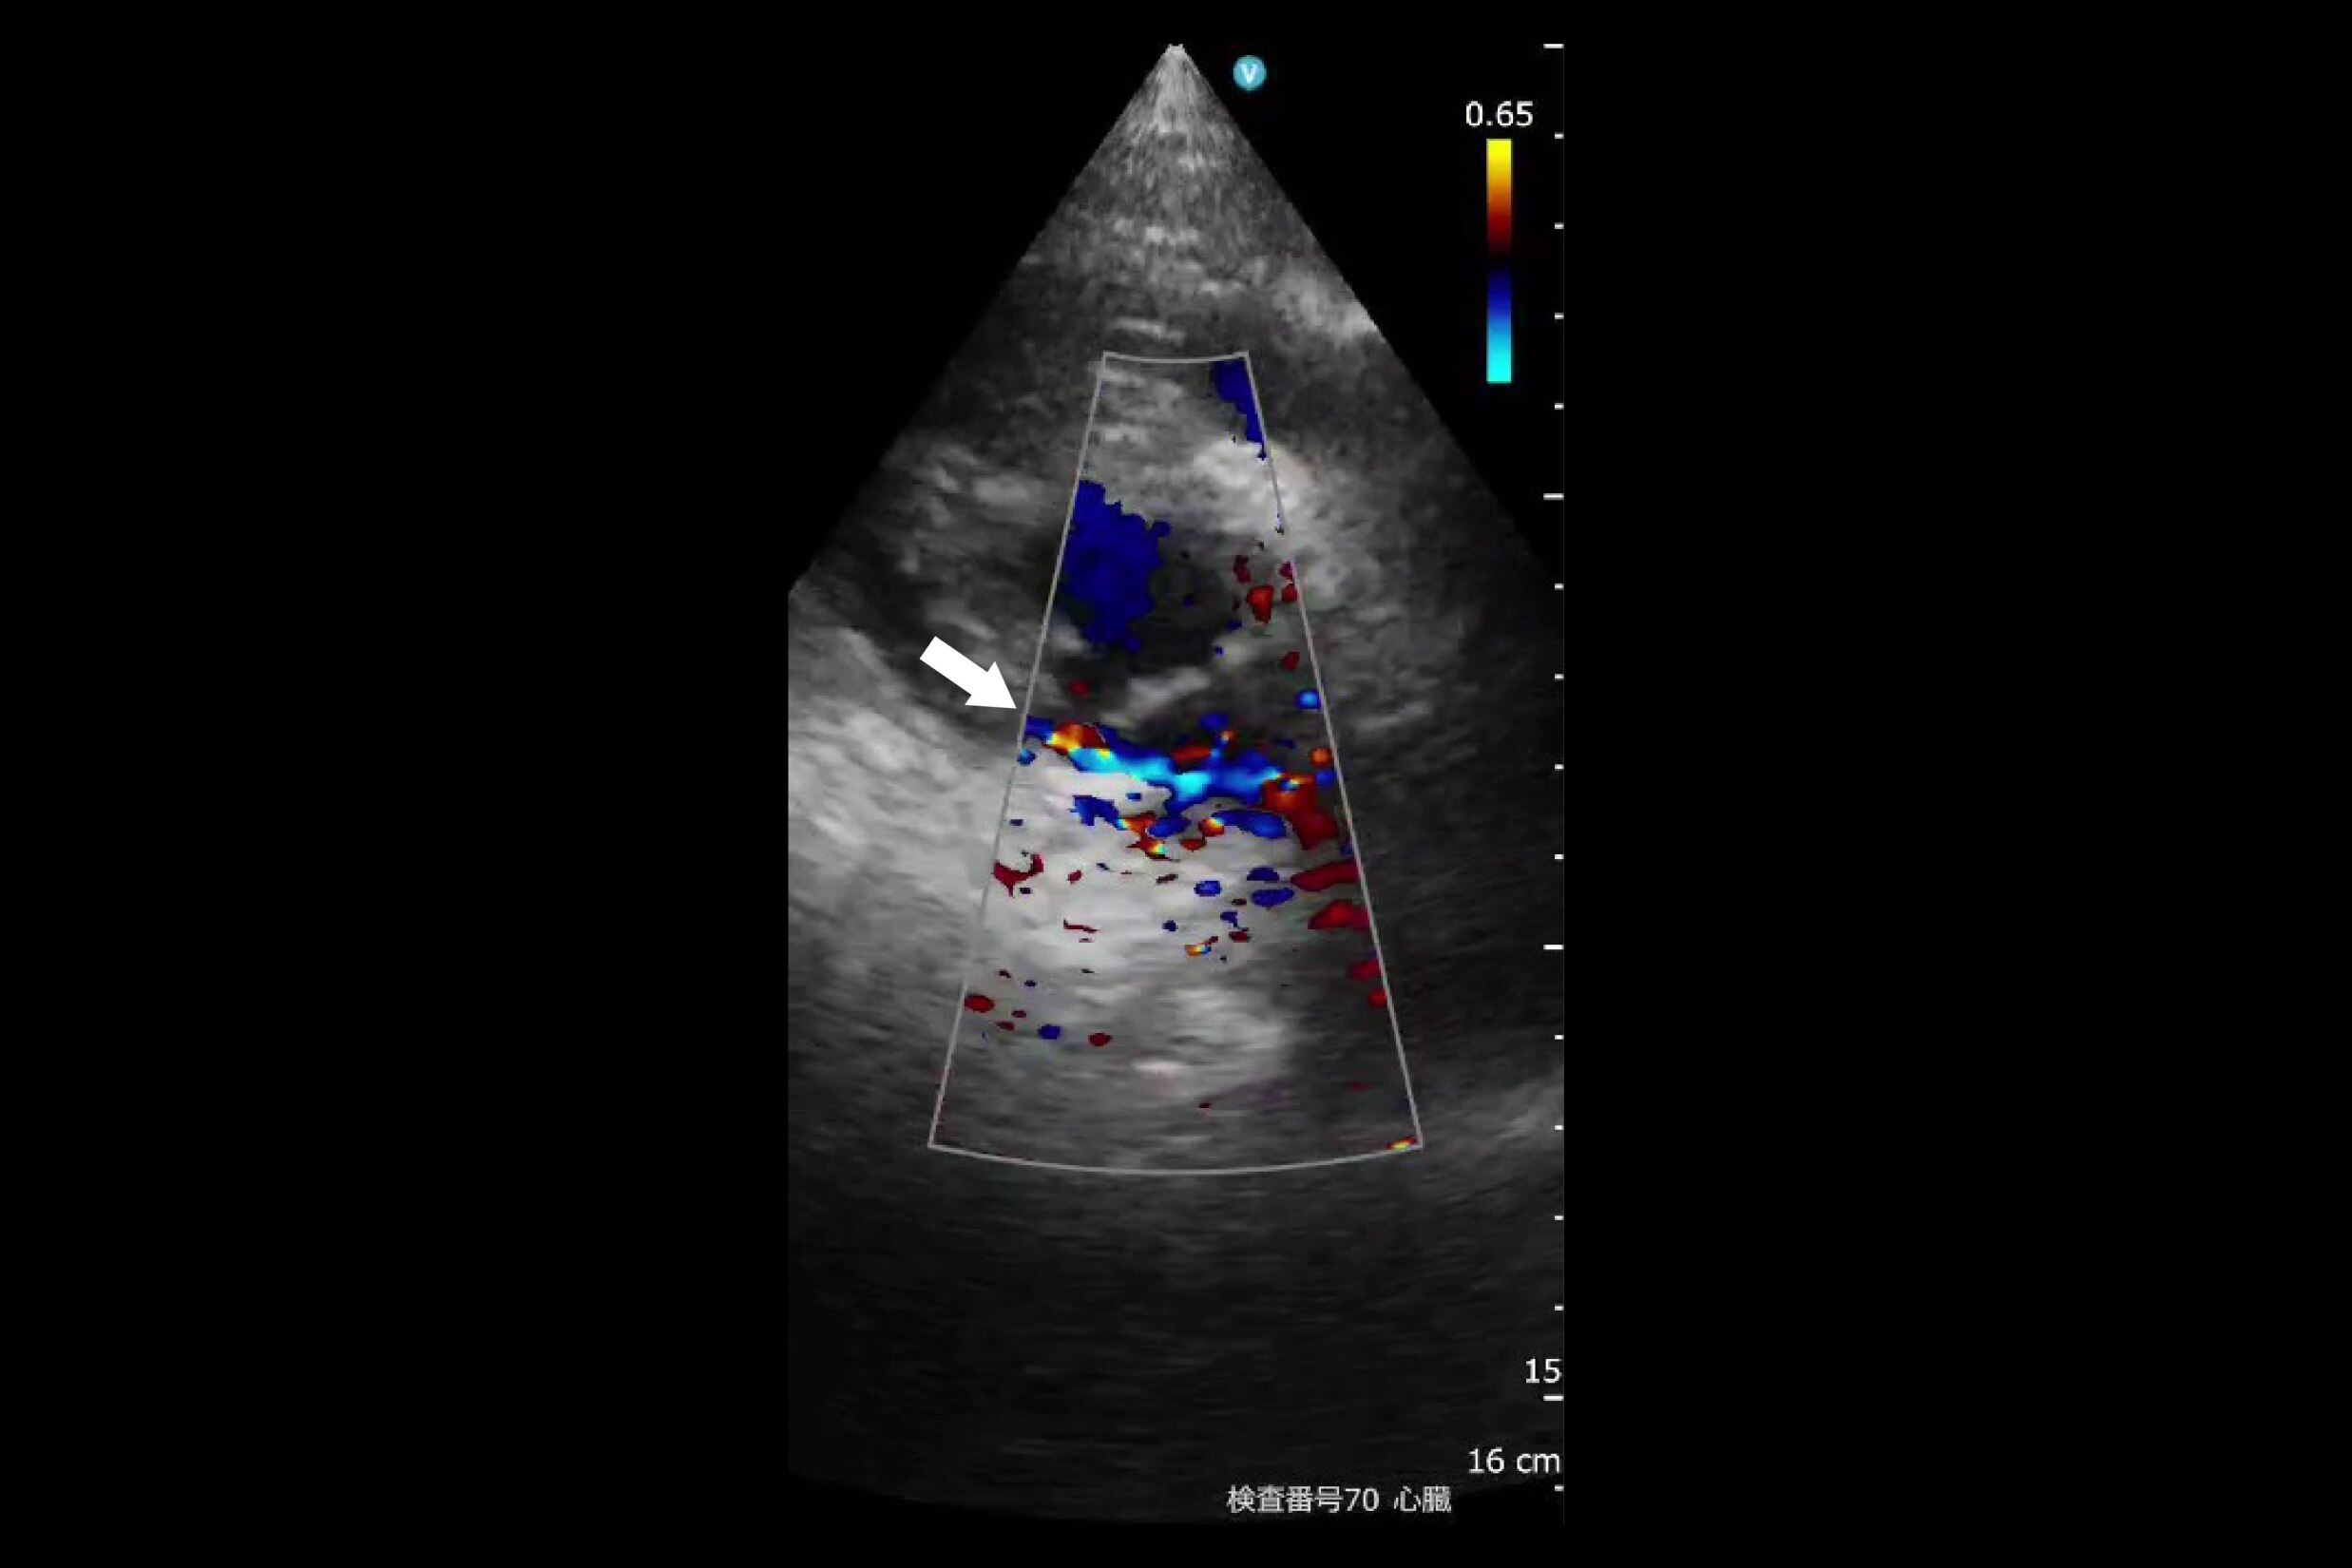

②は僧帽弁閉鎖不全(MR)と診断した88歳女性の画像。心不全の既往歴を持ち、呼吸不全と下肢の浮腫、収縮期雑音があったため、エコーで確認し、著明な心不全と診断した。利尿剤の投与を継続したところ浮腫と呼吸不全が改善、酸素投与量も毎分2Lから0.5Lに改善した。画像は利尿剤投与により呼吸不全改善後に実施したエコー検査によるもの。左心房の拡大や僧帽弁閉鎖不全(MR)が認められた。

②MR(僧帽弁閉鎖不全) 88歳女性

診断:心不全の既往歴、呼吸不全と下肢の浮腫、収縮期雑音あり。エコーで著明な心不全

対応:利尿剤の継続で改善、呼吸不全著明に改善

予後:利尿剤継続、在宅酸素2L→0.5Lに改善